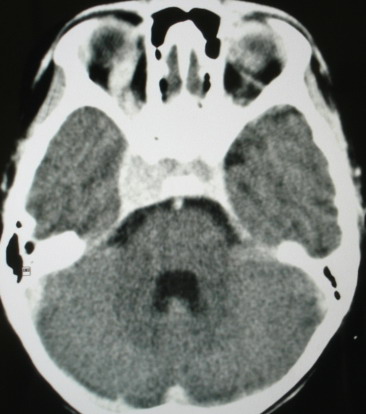

m/8y/,右侧眼睑下垂数日,发育良好,无外伤史,无头痛、恶心、呕吐,学习成绩良好。

ct意见:1、颅内血管畸形。2、右侧海绵窦血管瘤(颈内动脉海绵窦段动脉瘤)。3、脑萎缩。4、建议mr或dsa.

增强片

海绵窦瘘.注意眶内静脉有扩张.

右侧海绵窦血管瘤伴右侧海绵窦漏形成(由于右眼上静脉较左侧增粗。故考虑)。

支持 右侧颈内动脉海绵窦瘘.注意眶内静脉有扩张.